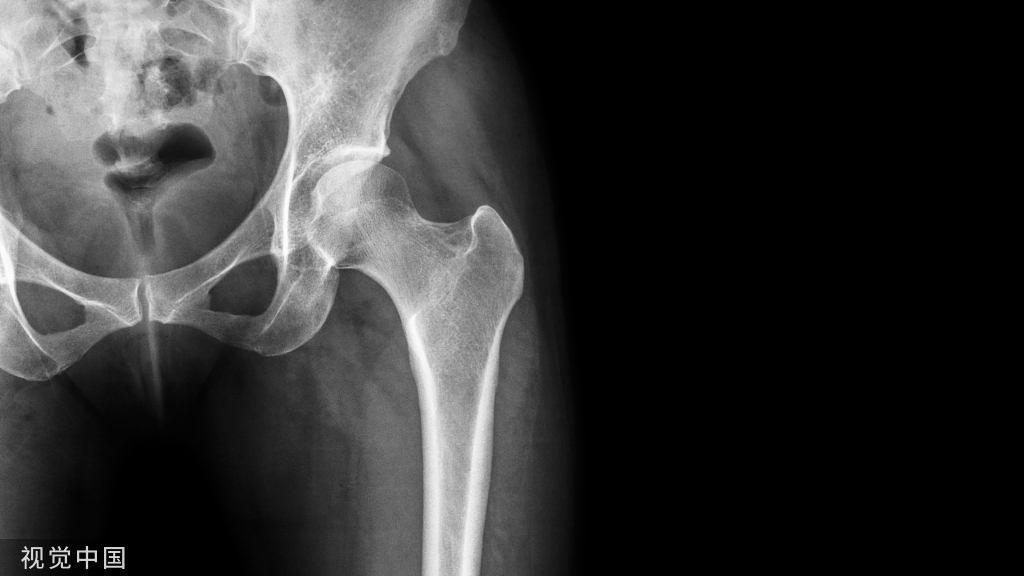

病例简介:患者,男,19岁。因车祸致伤左髋部,伤后4小时来北京积水潭医院急诊,经体检拍片(图62-1),诊断为股骨颈骨折(左,GardenⅣ型)。

图62-1 股骨颈骨折患者术前及术后系列X线片A、B.术前正侧位X线片;C、D.术后当日正侧位X线片;E、F.术后10周正侧位X线片,显示骨折已愈合

术后复查时可发现“钉尾外退”现象,轻度退钉是愈合过程骨折端吸收所致,不影响骨折愈合。对于退钉较多者,应嘱患者停止负重。骨折愈合后,应每3~6个月复查一次,直至术后3年,以便早期发现股骨头缺血坏死。术后第一天下地,扶双拐部分负重至术后2个月改用单拐,术后3个月弃拐完全负重行走。骨折于术后10周愈合,至术后5年未发生股骨头缺血坏死(图62-1)。